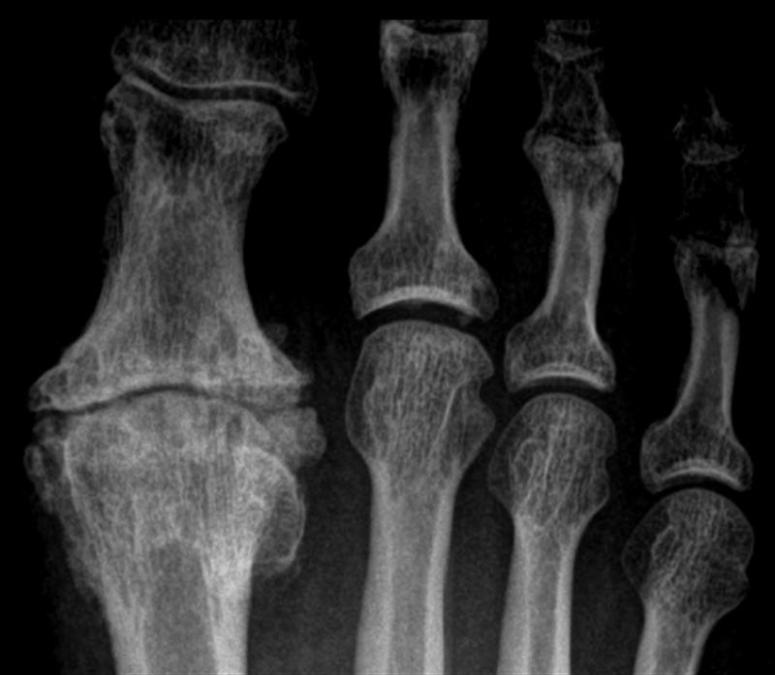

Severe Hallux Rigidus Advanced Foot And Ankle Center Of San Diego Foot Health Facts Hallux Rigidus It is due to a wearing. hallux rigidus means “stiff big toe” — the condition’s most common symptom. It causes pain and stiffness in. early signs of hallux rigidus include pain and stiffness in the big toe joint during use, such as walking or exercising,. hallux rigidus (stiff big toe) occurs when the joint at the base. Foot Health Facts Hallux Rigidus.